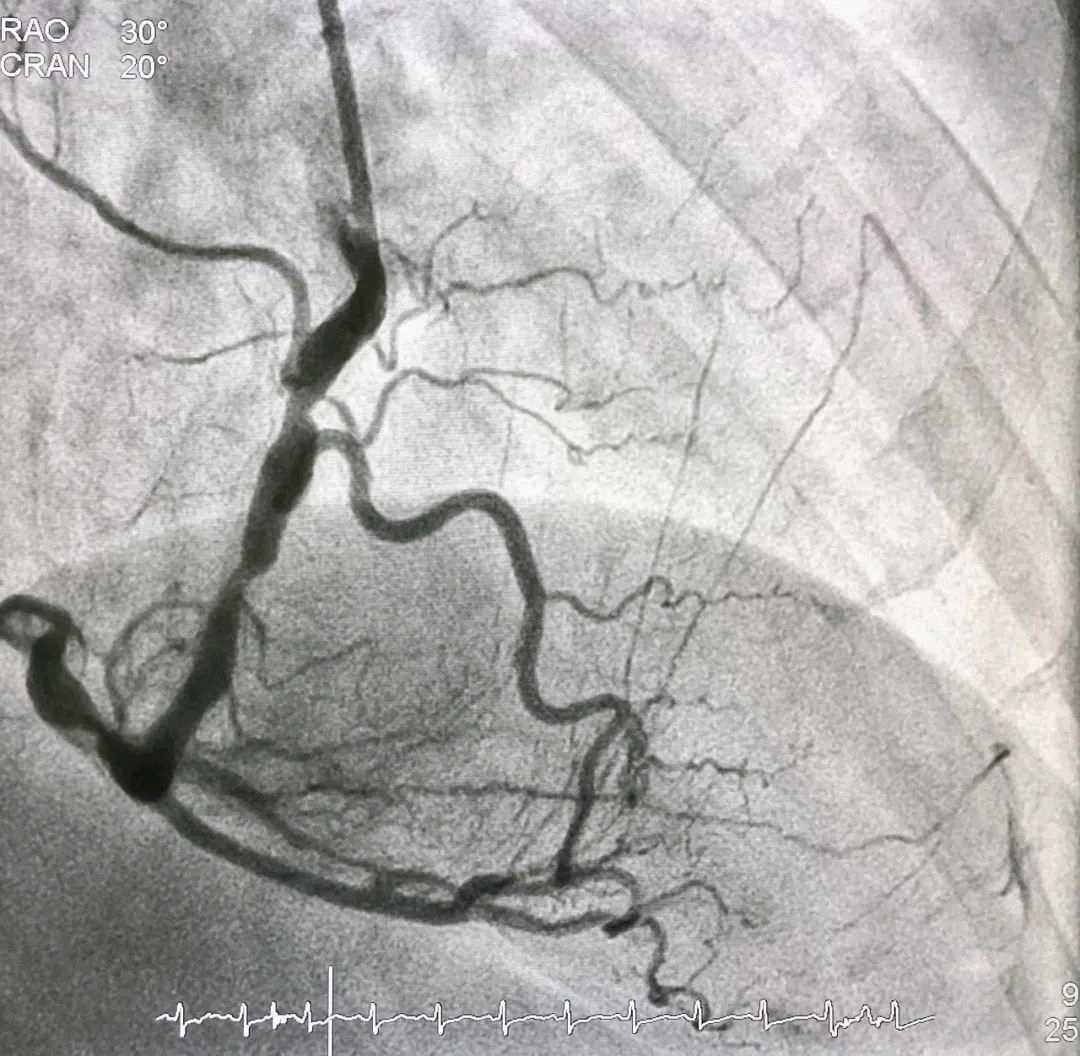

心肌缺血确诊的“金标准”是冠状动脉造影,从手上的桡动脉插根导管,插到心脏的冠状动脉,然后注射造影剂,显影后看冠状动脉有没有狭窄。有狭窄的话,再分析狭窄的程度,就会一目了然。